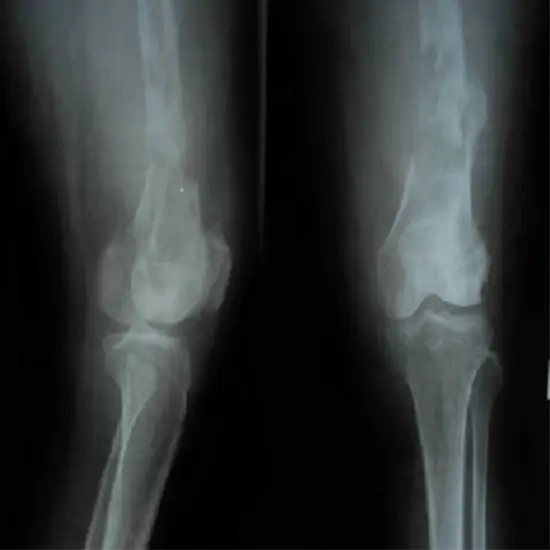

X-ray Right Thigh AP/LAT View

Thigh X-ray utilizes a minimal quantity of radiation to create a picture of the upper leg.

Upper leg symptoms such as discomfort, limp, soreness, edema, or deformity may be diagnosed using a thigh X-ray. It can identify a fracture, and once a fracture has been fixed, it can assist in establishing whether the bone is aligned correctly. If surgery of the upper leg is necessary, an X-ray may be performed to plan and evaluate the procedure's outcome. X-rays may be used to identify cysts and tumors.